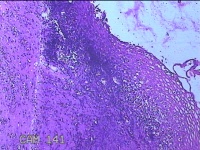

宫颈2点、3点、9点组织

性别

女

年龄

38岁

临床诊断

人乳头瘤病毒感染

一般病史

宫颈其他HPV12阳性

标本名称

大体所见

1.“宫颈2点组织”:灰白粉红色组织0.8x0.5x0.2cm一块。 2.“宫颈3点组织”:灰白粉红色组织0.7x0.5x0.2cm一块。 3.“宫颈9点组织”:灰白粉红色组织0.7x0.5x0.2cm一块。

图4